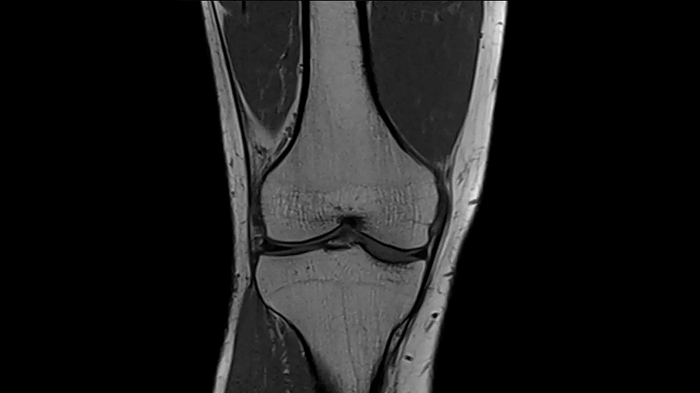

Knee

T1 SE

Outstanding T1 imaging of the knee using MAGNETOM Free.Star.

0.3 x 0.3 x 3.0 mm2

TA 2:54 minutes

MAC-ID: 7aaaa0198. Image Credit: Siemens Healthineers

3D MSK Imaging with Compressed Sensing

Knee imaging with T2w SPACE can be expedited using Compressed Sensing to reduce acquisition times, offering high-resolution images for uncompromised knee assessments.

Compressed Sensing 6

0.3 x 0.3 x 0.6 mm2

TA 4:15 minutes

MAC-ID: 7aaaa0175. Image Credit: Siemens Healthineers